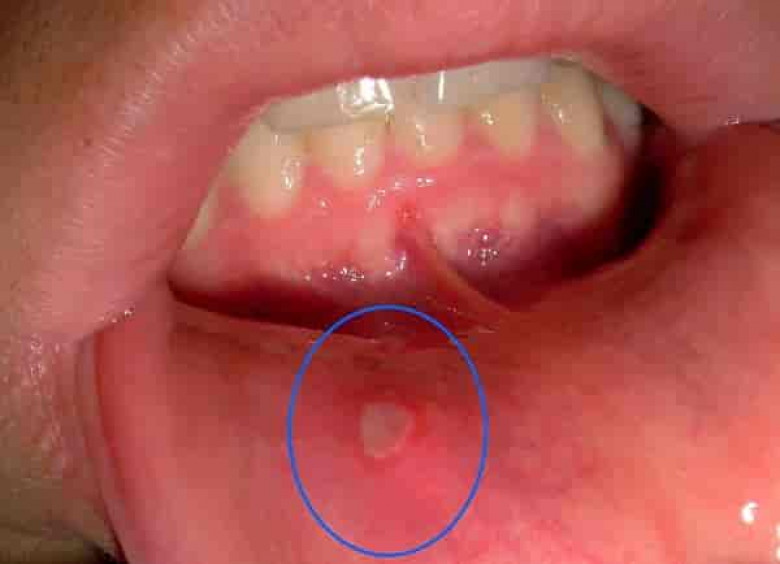

4 Եղունգները կրծելով դուք կարող եք վնասել լնդերը և լեզվի լորձաթաղանթը և անմիջապես վարակ անցկացնեք վերքի մեջ: Եղունգների տակ գտնվող ստաֆիլակոկները ջանասիրաբար կաշխատեն բերանում ստոմատիտ առաջացնելու վրա: